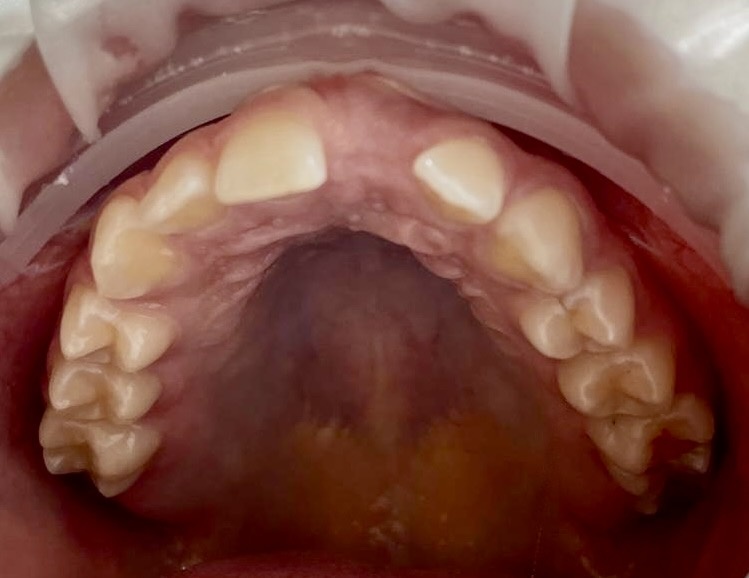

Коронковая часть зуба 2.1 (верхний левый резец) в полости рта не визуализируется. Выглядит как "дырка".

На снимке КЛКТ (нет в доступе, найду позже и поделюсь в своём тг канале) было обнаружено, что зуб-то в кости есть. Уже хорошо.

Минус - покрыт костной тканью полностью.

Плюс - добыть его можно.

Пациентка направлена к хирургу, который создал для ортодонта доступ к зубу - разрезал десну и выпилил костное окно.